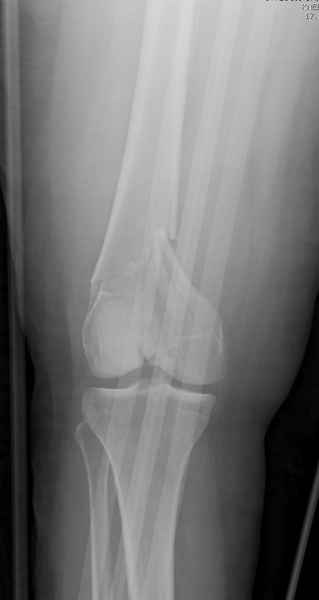

Привет из Нижнего Новгорода! К нам поступил пациент 25 лет с закрытыми переломами обеих бедренных костей, прошел месяц после травмы. Слева - внутрисуставной перелом, поэтому выбор здесь очевиден, открытая репозиция, стабильная фиксация, скорее всего LCP DF, а справа - мнения учёных, как говорится, разошлись. Лично я, как лечащий врач, за закрытый интрамедуллярный остеосинтез DFN. Со мной согласна половина коллектива, другая - за интрамедуллярный остеосинтез (DFN,UFN) но с открытой реопозицией, поскольку при закрытой методике все осколки останутся где-то сбоку, получится дефект и вдруг не срастется!Философский вопрос: что лучше - красивая рентгенограмма или сохранение кровоснабжения? Очень важно мнение коллег! Смирнов Алексей

Приветствую всех коллег!!Во первых слева хотелось бы видеть четкую боковую проекцию а лучше КТ. По р-мам есть сомнения насчет повреждения суставной поверхности. При подобных переломах даже внутрисуставных без смещения хорошие результаты показал закрытый ретроградный остеосинтез универсальным бедренным стержнем Деост.Кстати при внутрисуставном переломе возможно применение вместо винтов стягивающих болтов!!(См. метод.Деост).При переломе справа также стержень Деост. Однако без открытия Вам не удастся устранить интерпозицию, только промучаетесь!Из минимального разреза удалите интерпозициб и фиксируйте стержнем. Причем универсальный стежень Деост позволяет фиксировать дистально минимум на трех уровнях!